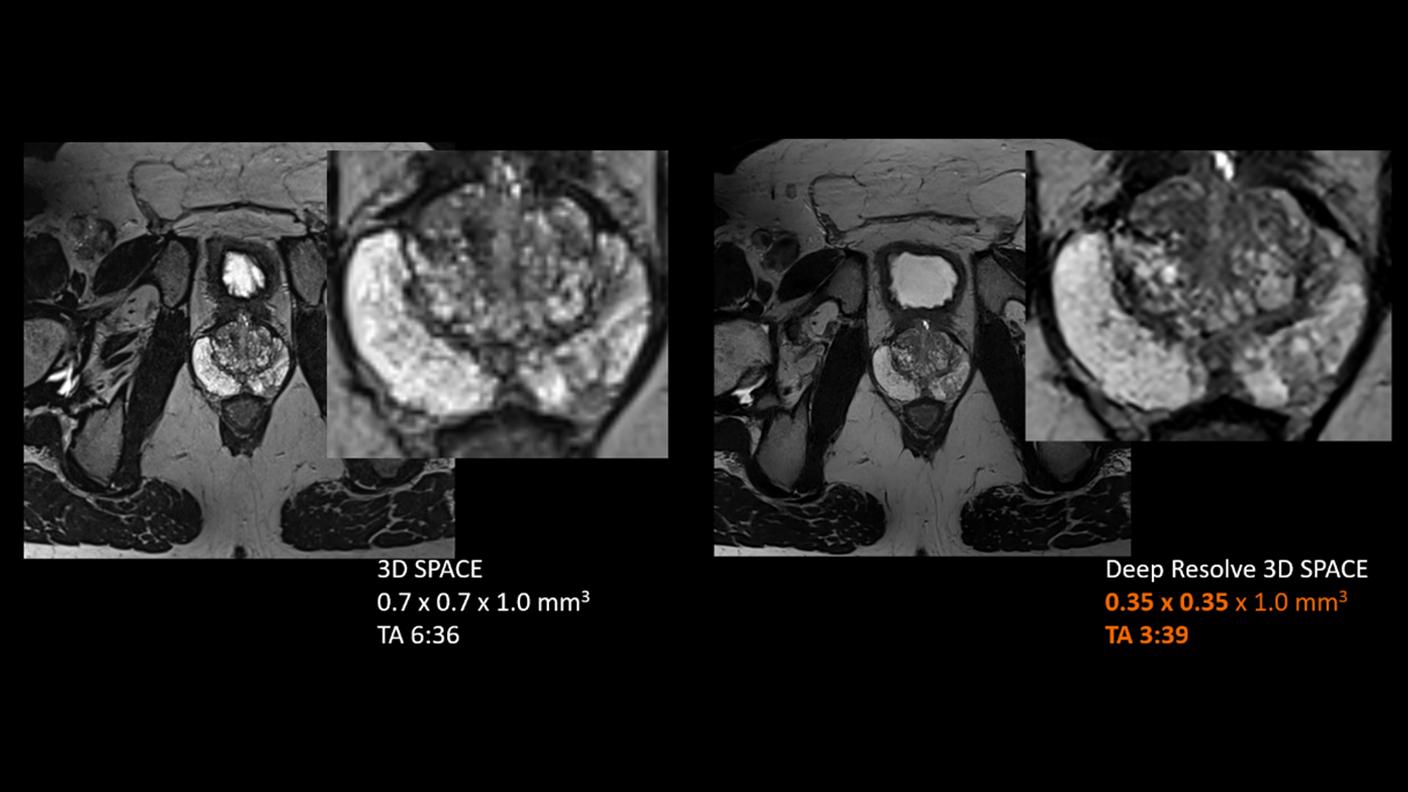

AIを活用した高画質3D撮像と自由呼吸下での全身造影Dynamic評価により、微小がんの検出から腫瘍性状・広がりの把握までを、高精度かつ検査効率向上と被検者負担軽減の両立を図りながら支援し、がん診療全体の質向上に貢献します。